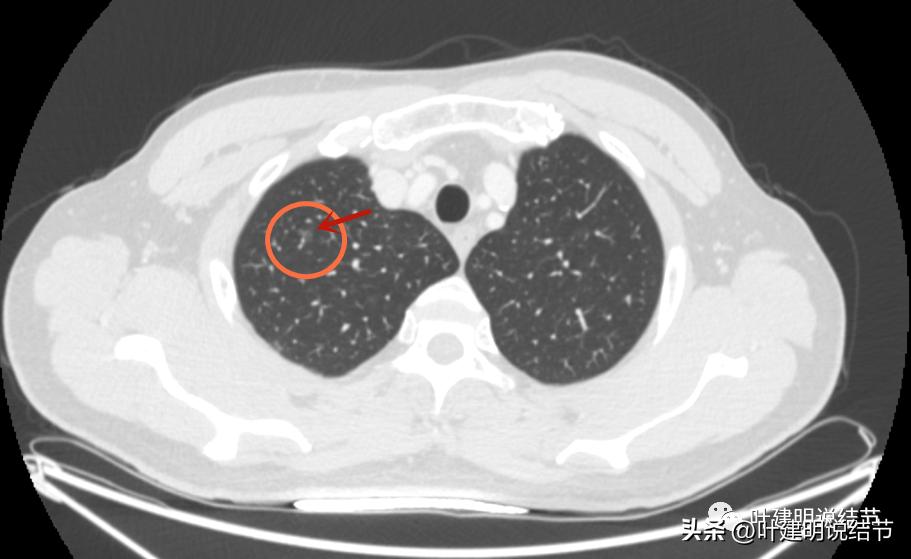

病灶2:右上叶结节

右上有微小磨玻璃结节,见血管穿行,整体密度也不高,但似乎比左侧的略高点。

病灶轮廓较清。

这两处结节均考虑是肿瘤范畴的,因为轮廓清,磨玻璃密度,并有血管穿行。但整体均还上,密度还很低,尤其左侧的密度更低。这样密度极低的磨玻璃结节,它周围的血管贴边并不似因为肿瘤生长需要富血供,从而吸引了新生血管过来,或周围血管发出分支来供血,而是“碰巧”有血管刚好经过的可能性更大些,且淡磨玻璃密度的结节基本不具有侵袭性,不至于侵犯或影响血管从而带来危险。如果一定要来预估一下病理会是什么,大概左侧以不典型增生可能性大,不能除外原位癌;右侧稍倾向原位癌,但也可能是不典型增生或肺泡上皮增生,至少近期风险低,能随访。

左侧磨玻璃结节红色圈起来的瘤肺边界清,有血管贴边,但整体密度低,没有实性成分,考虑仍是不典型增生或原位癌阶段,近期风险低,个人觉得最好先随访,因为可能很多年不变的,而且也可能再检出新的结节来。况且随访有进展再干预,效果也是一样的。右侧结节也是肿瘤范畴,但风险一样不高,建议同样半年到一年复查(其实1年也关系不大的)。意见供参考!